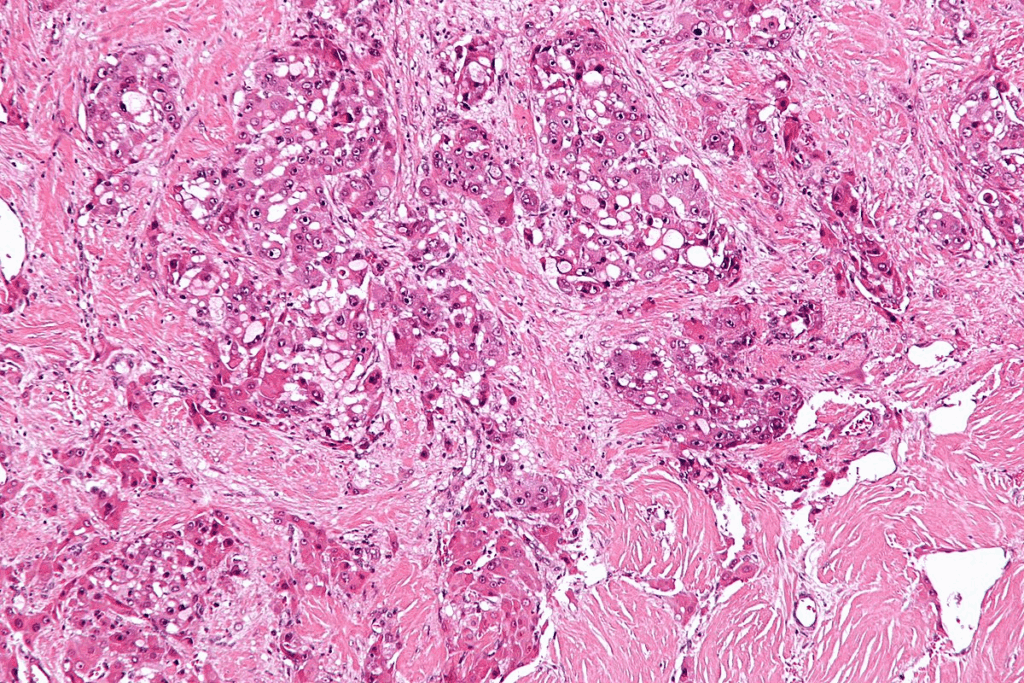

To understand CIS bladder cancer, we must look at its cell features and molecular markers. Carcinoma in situ (CIS) is a serious, non-invasive bladder cancer. It hasn’t broken through the basement membrane yet. Knowing about its pathology helps in early detection and treatment.

The features of CIS are key for its diagnosis. CIS shows marked nuclear enlargement, hyperchromasia, and loss of cellular polarity in the urothelium. These abnormal cells stay in the epithelial layer and haven’t invaded deeper tissues. The urothelium looks disordered or chaotic, with cells showing a lot of pleomorphism.

Looking at the cells under a microscope is vital to tell CIS apart from other bladder issues. The diagnosis of CIS relies on these specific cell features.